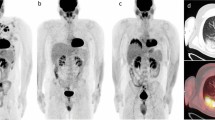

Randomization was based on the iPET evaluation using the delta-SUVmax method. Patients with a decline of FDG uptake >66% in the most FDG-avid lesion compared to the baseline scan were regarded to have a negative interim PET scan; patients with a lesser decline, an increase, or new lesions were considered to have a positive scan (Fig. 2).

In case of a negative interim PET result, patients were randomized to receive either 6xR-CHOP or 6xR-CHOP plus two additional rituximab administrations. A negative interim PET scan was defined as an SUV decrease >66% of the most FDG-avid lesion compared to the baseline scan. Patients with a positive interim scan were randomized to receive either 8x(R-)CHOP or 2x(R-)CHOP followed by 6 blocks of the Burkitt protocol (R was restricted to CD20-positive lymphomas) (A). The interim PET scans were re-evaluated using an AI-based software to automatically quantify FDG uptake (B). Patients with a positive interim PET had statistically significantly higher mean-SUVAI compared to those with a negative interim PET (C).

The manual image analysis of the PETAL trial was used for comparison. For re-analysis, the neural network-based PET-assisted reporting system software prototype (PARS) was employed (Siemens Healthineers, Knoxville, TN, USA). The tool is distributed by Siemens upon request. The AUC of this fully automated neural network used for the segmentation of all lymphoma manifestations is 0.95 (95% confidence interval CI: 0.92–0.97), as previously published [12]. PARS identifies all FDG-PET foci with elevated uptake and rates each as either pathological or physiological, using the pretrained networks (Fig. 2). All lymphoma manifestations can thus be segmented fully automatically.